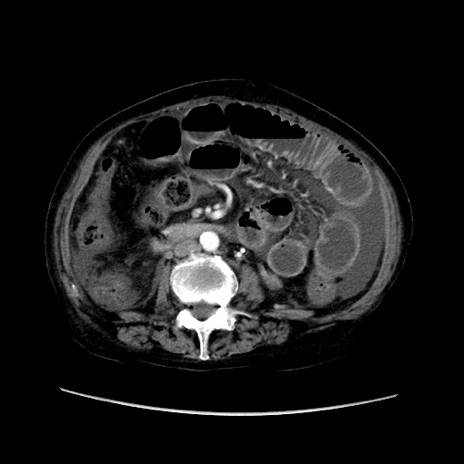

症例31(横断像)

【症例】80歳代 女性

【主訴】腹部膨満感

【現病歴】他院にて肝硬変にてフォロー中。1週間前から便秘、腹部膨満感、臍部腫瘤あり受診となる。

【既往歴】肝硬変

【身体所見】腹部膨隆あり、皮膚変化なし、疼痛なし。

【データ】WBC 4600、CRP 0.25